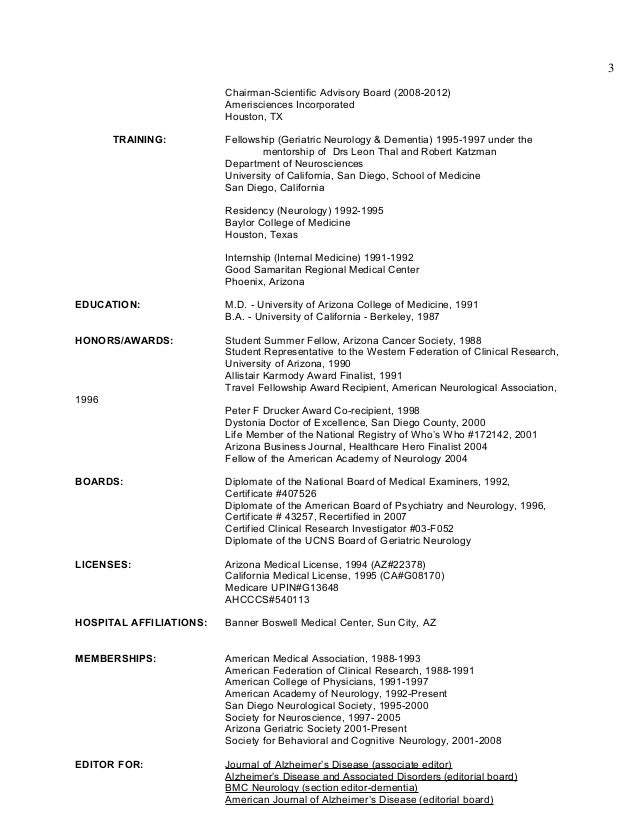

Marwan S Cv Updated March 12 2015